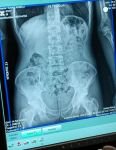

İl Emniyet Müdürlüğü Narkotik Suçlarla Mücadele Şube Müdürlüğü ekipleri tarafından Doğu illerinden İstanbul’a giden bir yolcu otobüsü polis ekipleri tarafından şüphe üzerine kontrol noktasında durduruldu. Yolcu otobüsünde bulunan bir kişinin şüpheli davranışlar sergilemesi dikkat çekti. 41 yaşındaki işçi Şefik B'nin uyuşturucu maddeyi kapsüller halinde yutarak taşıdığı tespit edildi. Şüphelinin çekilen röntgeninde midesinde çok sayıda kapsül olduğu belirlendi. Şüphelinin midesinden 48 parça kapsül halinde 542 gram eroin çıkarıldı.